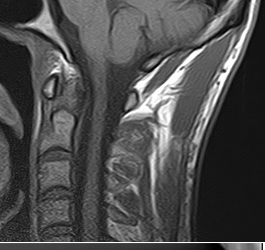

Radiologie - Echographie - Mammographie - Scanner - IRM

Scanner, IRM, échographie, radiographie... Injection d'iode, de gadolinium...